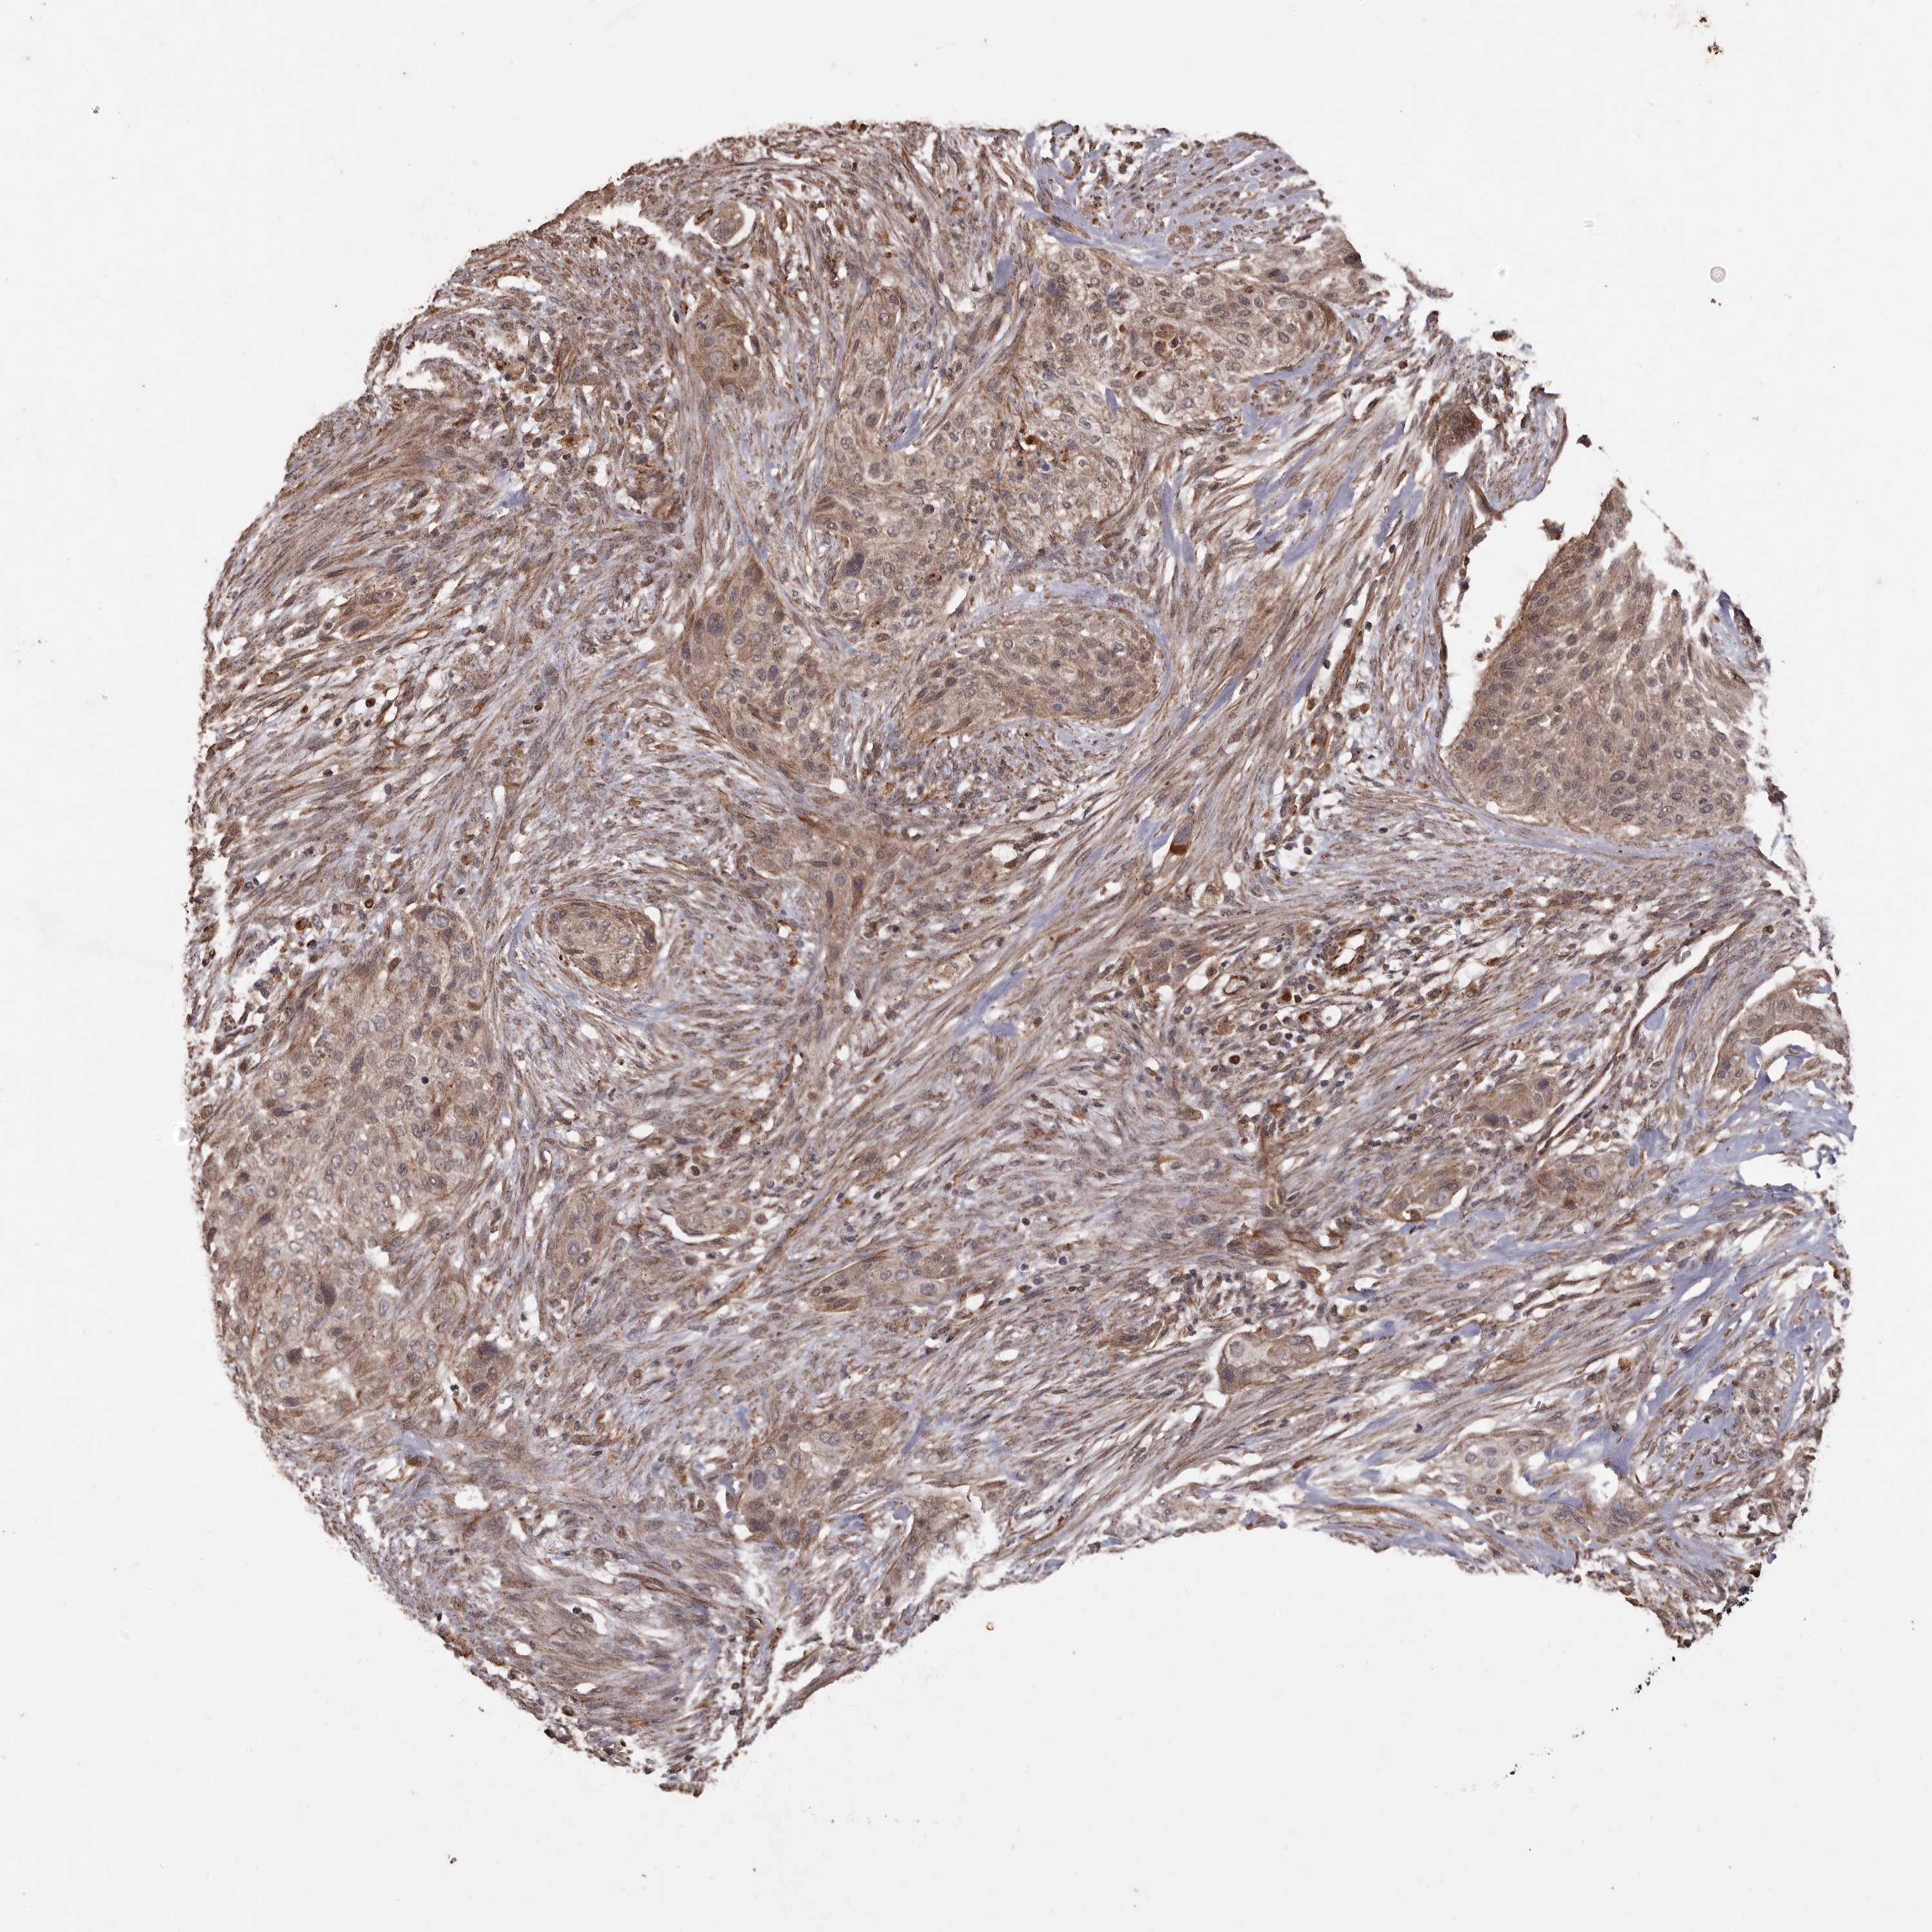

UROTHELIAL CANCER - Protein expressioni

A mouse-over function shows sample information and annotation data. Click on an image to view it in a full screen mode. Samples can be filtered based on level of antibody staining by selecting one or several of the following categories: high, medium, low and not detected. The assay and annotation is described here.

Note that samples used for immunohistochemistry by the Human Protein Atlas do not correspond to samples in the TCGA dataset.

Antibody stainingi

Antibody staining in the annotated cell types in the current human tissue is reported as not detected, low, medium, or high, based on conventional immunohistochemistry profiling in selected tissues. This score is based on the combination of the staining intensity and fraction of stained cells.

Each image is clickable and will lead to virtual microscopy that enables deeper exploration of all samples and also displays staining intensity scores, fraction scores and subcellular localization as well as patient and tissue information for each sample.

Antibody HPA029455

Staining

High

Medium

Low

Not detected

Intensity

Strong

Moderate

Weak

Negative

Quantity

>75%

75%-25%

<25%

None

Location

Nuclear

Cytoplasmic/membranous

Cytoplasmic/membranous,nuclear

Urothelial carcinoma, Low grade

Urothelial carcinoma, High grade